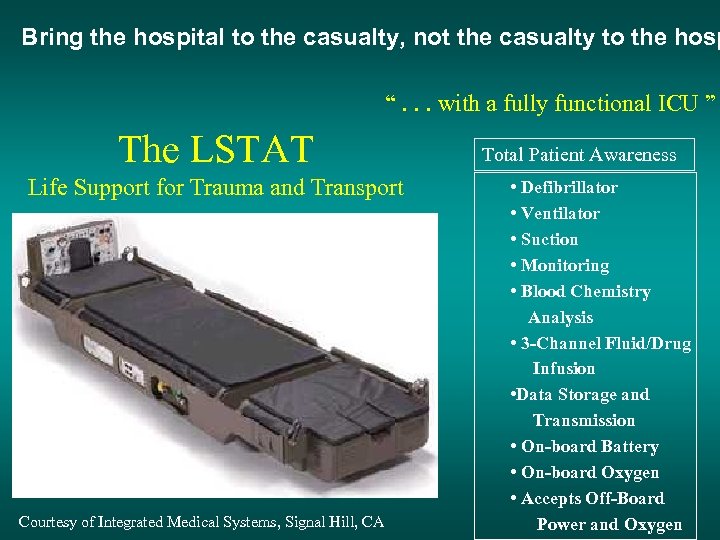

Bring the hospital to the casualty, not the casualty to the hosp “. . . with a fully functional ICU ” The LSTAT Life Support for Trauma and Transport Courtesy of Integrated Medical Systems, Signal Hill, CA Total Patient Awareness • Defibrillator • Ventilator • Suction • Monitoring • Blood Chemistry Analysis • 3 -Channel Fluid/Drug Infusion • Data Storage and Transmission • On-board Battery • On-board Oxygen • Accepts Off-Board Power and Oxygen

Bring the hospital to the casualty, not the casualty to the hosp “. . . with a fully functional ICU ” The LSTAT Life Support for Trauma and Transport Courtesy of Integrated Medical Systems, Signal Hill, CA Total Patient Awareness • Defibrillator • Ventilator • Suction • Monitoring • Blood Chemistry Analysis • 3 -Channel Fluid/Drug Infusion • Data Storage and Transmission • On-board Battery • On-board Oxygen • Accepts Off-Board Power and Oxygen